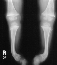

- Multiple rachitic deformities of the skeleton to include severe bowing

of the tibias bilaterally (45 degrees), pigeon chest (pectus carinatum),

thickened/widened wrists bilaterally and a trendelenberg gait on the left

side.

X-RAY STUDIES:

- "cupping" of the distal radius and distal femur

- widening of the physis

- angular deformities